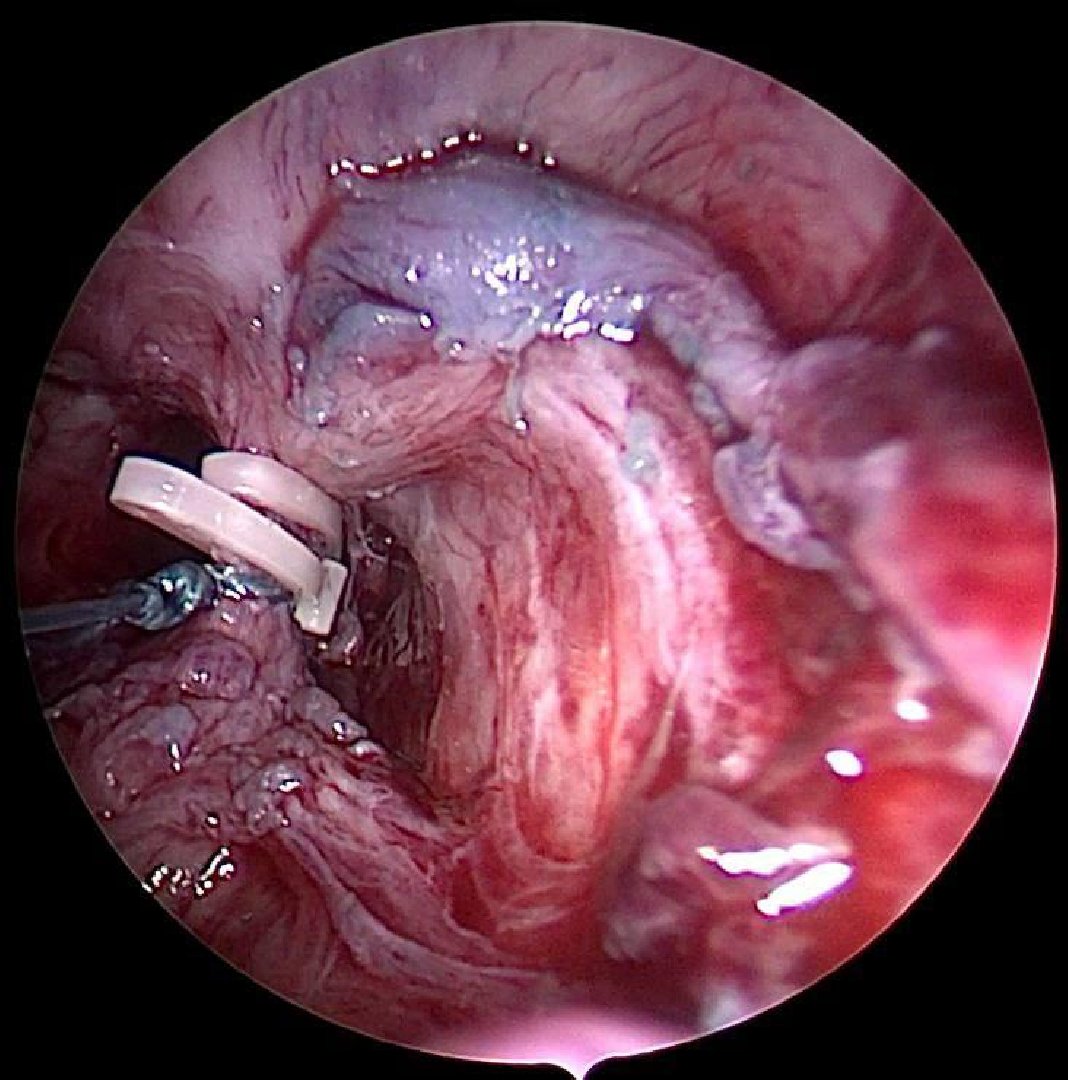

«Урологи МОЦОМД выполнили сложнейшую операцию, длившуюся более четырёх часов. При этом они применили минимально инвазивные технологии – цистоскопию и лапароскопию. Хирурги иссекли свищ, разъединив сообщение между прямой кишкой и мочевым пузырём», – пояснил заведующий уроандрологическим отделением Андрей Суходольский.На десятые сутки маленького пациента выписали на амбулаторное лечение. Сейчас он чувствует себя хорошо.